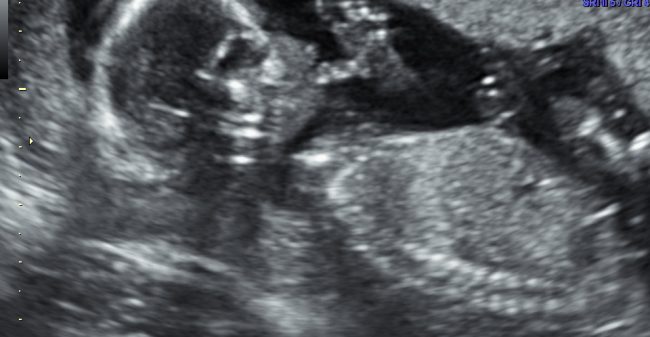

Als je zwanger bent, kun je natuurlijk niet wachten totdat je je kindje kunt zien. En je wilt weten of de ontwikkeling van je baby goed gaat. Door middel van een echo kun je kennismaken met het kindje in je buik!

Prenataal Centrum Alkmaar (PCA) is een kleinschalig, cliëntvriendelijk echocentrum waar gedurende de hele zwangerschap, van 6 tot 36 weken, verschillende echo’s kunnen worden gemaakt; zowel medische screening als op eigen verzoek. Omdat wij alle drie verloskundige en zelf ook moeder zijn, begrijpen we goed wat ervoor nodig is om een waardevolle belevenis van een echoscopisch onderzoek te maken: persoonlijke aandacht, professionele technologie en uiteraard een flinke dosis ervaring en vakkennis!Wij werken samen met verschillende verloskundigenpraktijken uit de regio, maar ook op eigen initiatief kan een echo worden afgesproken.Zo kan het geruststellend zijn om vroeg in de zwangerschap hartactie bij de embryo aan te tonen. Of kan het leuk zijn om een keer met ‘opa en oma’ naar hun aanstaande kleinkind te komen kijken en bijvoorbeeld tussen 26 en 32 weken voor een 3D-pretecho met DVD-registratie te komen. Natuurlijk zijn kinderen hierbij ook welkom! Door onze ruime openingstijden, ook in avonduren en op zaterdag, is er veel mogelijk. Het geeft veel voldoening om aanstaande ouders in beeld en uitleg mee te nemen in het verhaal van de ontwikkeling van hun kindje. Hiervoor maken we gebruik van de nieuwste technologie in 2D, 3D en 4D om een fotoserie op USB te maken en/of te filmen hoe de baby bijvoorbeeld zijn duimpje zoekt, of lacht. Bij de afname van meerdere echo’s bieden wij voordeelpakketten aan.